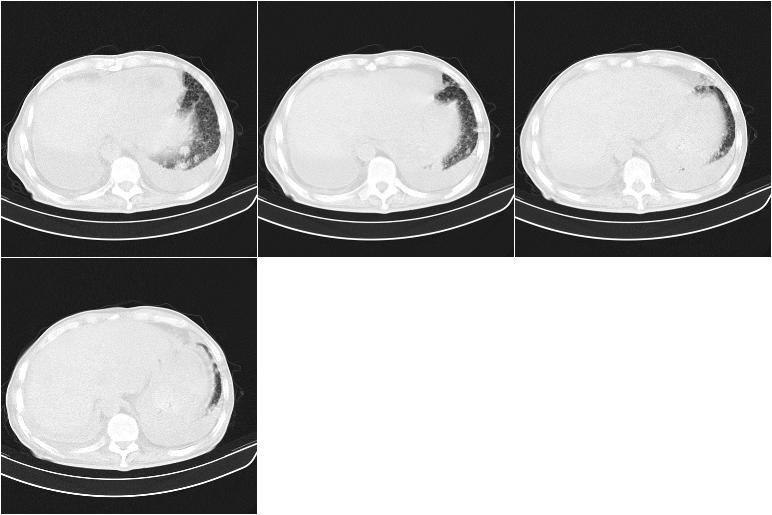

以下是引用边生丽在2009-8-17 11:43:00的发言:[br][br] [br] 右肺中心型癌伴右肺下叶不张、双肺转移并癌性淋巴管炎、心包和双侧胸腔积淮(转移?)、脑转移、肝转移、多骨(颅骨、椎骨)转移。 [br] [br]

以下是引用奥特之父在2009-4-20 19:58:00的发言:[br]支持胰腺癌并转移性病变。

以下是引用随光逐影在2009-8-17 14:09:00的发言:[br]支持 右肺中央型癌伴右肺下叶肺不张,纵隔淋巴结转移,双肺转移并癌性淋巴管炎,心包和双侧胸腔积液,脑转移、肝转移、多发性骨(颅骨、脊椎)转移。